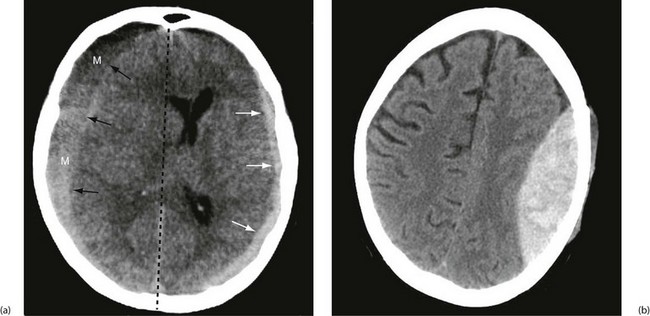

Focal injuries are the result of trauma to localised brain areas and are readily visible on CT scanning. The main lesions are cerebral contusion, laceration or haematoma, all of which may act as space-occupying lesions and are liable to result in secondary brain injury. The site and extent of the primary injury depend on the nature of the damaging force (see Fig. 16.2). Contusions may be small or large and occur either beneath the area of impact (coup) or contralateral to it (contre-coup), caused by rebound of the brain within the skull at the time of impact (Fig. 16.3). The severity of trauma required to cause focal brain injury will usually result in a period of loss of consciousness, followed by confusion.

Post-traumatic intracranial bleeding is classified into extradural (epidural), subdural, intracerebral or subarachnoid (see Fig. 16.4). Intracranial bleeding acts as a mass lesion causing a general rise in ICP, whilst local brain compression can cause focal neurological deficit. Untreated, raised ICP may cause ‘coning’. One or both temporal lobes herniate through the tentorium cerebelli, compressing the third nerve and midbrain, whilst herniation of the cerebellar tonsils through the foramen magnum compresses the medulla, causing neurological deterioration and often death. Rising intracranial pressure manifests initially with deteriorating conscious level. Late clinical signs are:

Subdural haematoma: Subdural haematoma usually results from tearing of veins passing between cerebral cortex and dura, or from injury to vessels on the surface of the brain. Blood accumulates in the large potential space between dura mater and arachnoid mater. The haematoma tends to spread laterally over a wide area (Fig. 16.6). In contrast to extradural haemorrhage, there is usually underlying primary brain injury. Acute subdural haemorrhage is more common in older adults because the brain is more mobile within the cranial cavity.

In an acute subdural haemorrhage, there is usually clinical evidence of brain injury at the outset. A lucid interval between initial loss of consciousness and later deterioration is rare, except where the pathology is tearing of a bridging vein. Evacuation of an acute subdural haematoma cannot be achieved via burr holes because the blood is clotted. Surgical evacuation via craniotomy may halt deterioration but recovery is often incomplete because of the underlying brain injury. With increasing use of anticoagulation and antiplatelet therapy, acute subdural haematoma is seen more commonly after relatively inconsequential injury, particularly in the elderly.

Intracerebral haemorrhage: Haemorrhage into the brain parenchyma is caused by primary brain injury. Multiple small deep lesions are often associated with diffuse axonal injury. Small haematomas should be managed conservatively and monitored for expansion using serial CT scans. A larger haematoma causing ‘mass effect’ should be evacuated early to prevent secondary brain damage.